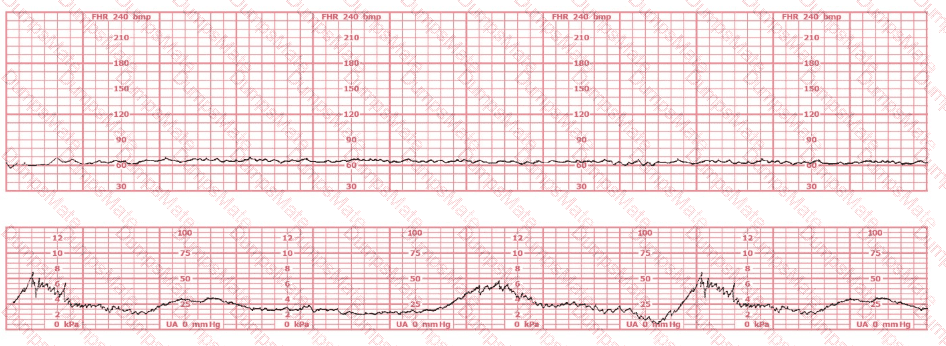

Questions 12

(Full question statement)

The fetal heart rate tracing shown is obtained upon the woman's admission to labor and delivery. This tracing is most consistent with what maternal condition?

EFM Question 12

Options:

A.

Eisenmenger's syndrome

B.

Sickle cell anemia

C.

Systemic lupus erythematosus

Buy Now